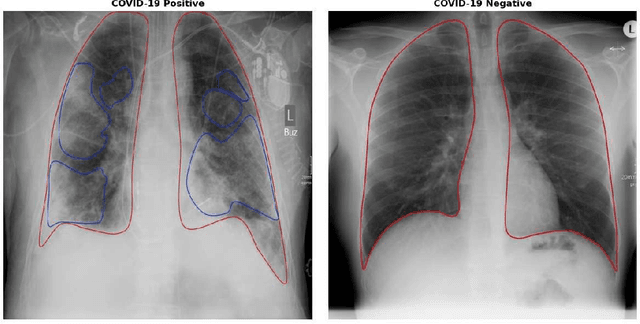

Abstract:Since the beginning of the COVID-19 pandemic, researchers have developed deep learning models to classify COVID-19 induced pneumonia. As with many medical imaging tasks, the quality and quantity of the available data is often limited. In this work we train a deep learning model on publicly available COVID-19 image data and evaluate the model on local hospital chest X-ray data. The data has been reviewed and labeled by two radiologists to ensure a high quality estimation of the generalization capabilities of the model. Furthermore, we are using a Generative Adversarial Network to generate synthetic X-ray images based on this data. Our results show that using those synthetic images for data augmentation can improve the model's performance significantly. This can be a promising approach for many sparse data domains.